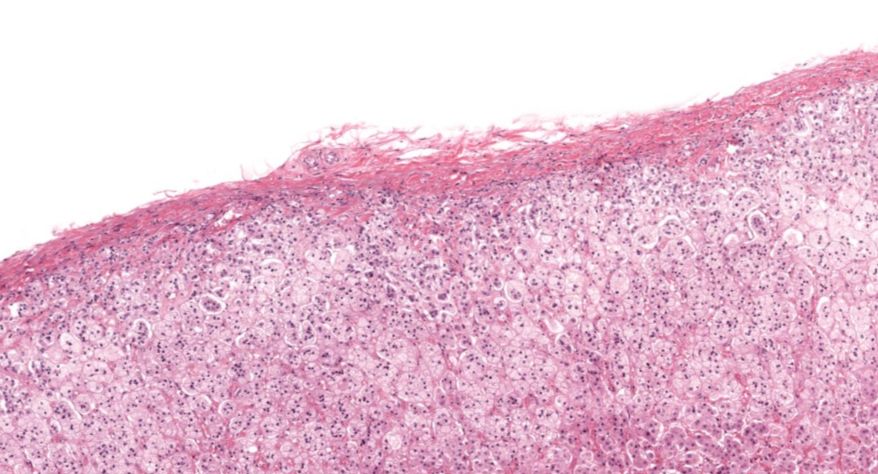

肾上腺

1.全景图

2.被膜

3.皮质